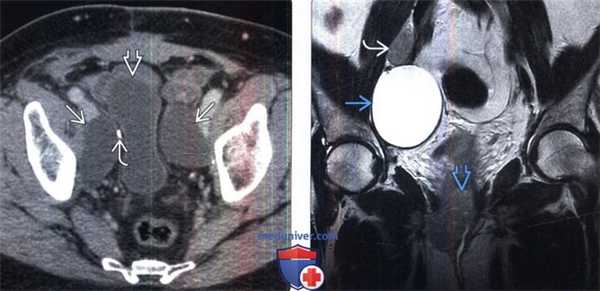

(Слева) КТ с контрастированием, аксиальная проекция: после простатэктомии выявлена компрессия мочевого пузыря двусторонним лимфоцеле. Обратите внимание на хирургическую клемму от лимфодиссекции.

(Справа) МРТ, Т2-ВИ, SS FSE, коронарная проекция: после гистерэктомии и лимфодиссекции по поводу рака шейки матки выявлено ограниченное лимфоцеле с высокой ИС на Т2-ВИ. Обратите внимание на рецидив первичной опухоли и прилегающий к уретре и метастаз в лимфатическом узле.